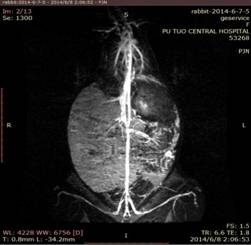

1、血管造影